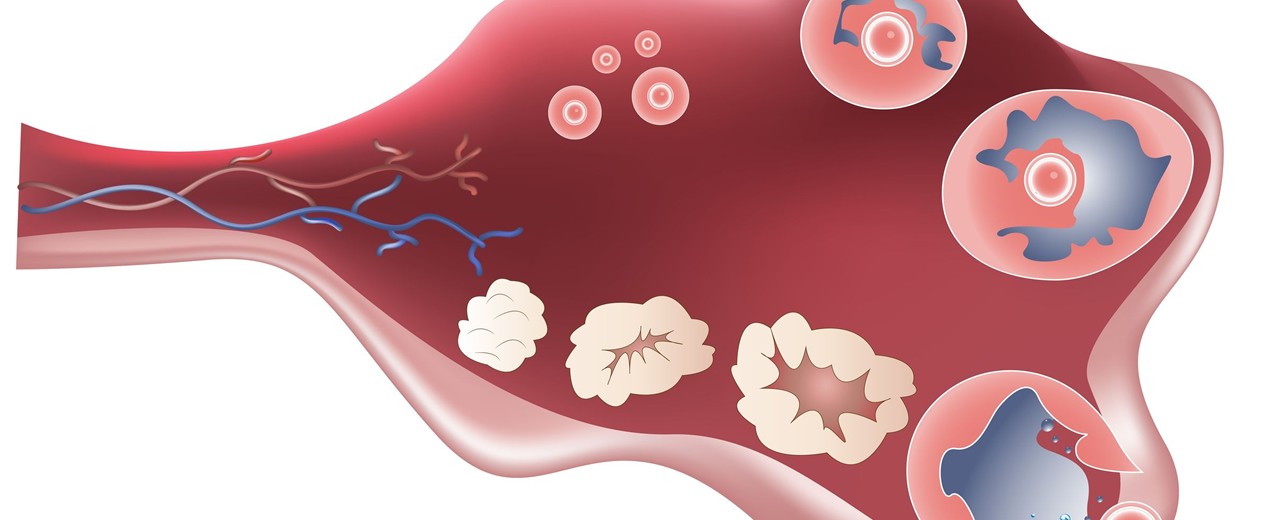

Τι είναι το σύνδρομο πολυκυστικών ωοθηκών (ΣΠΩ)

Οι ωοθήκες, όταν υπάρχει Σύνδρομο Πολυκυστικών Ωοθηκών, περιέχουν μεγάλο αριθμό αβλαβών «κυστών» ή...

Μια ματιά μέσα στη μήτρα σου κατά τη γονιμοποίηση

Η εγκυμοσύνη ξεκινά με τη γονιμοποίηση, όταν δηλαδή το ωάριο της γυναίκας ενωθεί με το σπερματοζωάριο του άνδρα. Τα ωάρια παράγονται από τις ωοθήκες, ενώ τα σπερματοζωάρια από τους όρχεις. Τα...